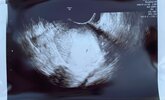

Widzicie ten maleńki kropek? 🥲

Pęcherzyk umiejscowiony bardzo ładnie po środku, piękne endometrium.

Wszystko jak powinno być 🥰